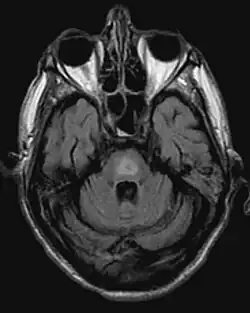

Zentrale pontine Myelinolyse, MRT-Bild des Gehirns axial in FLAIR-Wichtung; krankhaft ist der helle Ring in der Bild-Mitte